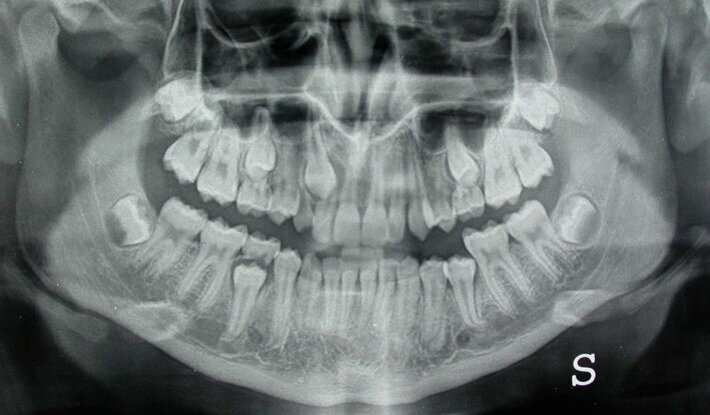

Le misure proposte da Ericson e Kurol sono state calcolate sulle radiografie panoramiche a T1 e T2, ovvero l’inclinazione mesiale della corona del canino rispetto alla linea mediana (angolo α); la distanza della punta della cuspide del canino permanente dalla linea occlusale (d); e la posizione mediale della corona nei settori 1-5 (s1-s5)9 (Fig. 1).

L’esito positivo della PDC è stato definito come la completa eruzione del dente, permettendo così il posizionamento del bracket per l’allineamento finale dell’arcata quando necessario. L’esito negativo era rappresentato dalla mancata eruzione del canino permanente (inclusione) al termine del periodo di osservazione clinica (48 mesi dopo l’osservazione iniziale), richiedendo così l’esposizione chirurgica e il trazionamento ortodontico (Figg. 2-13).